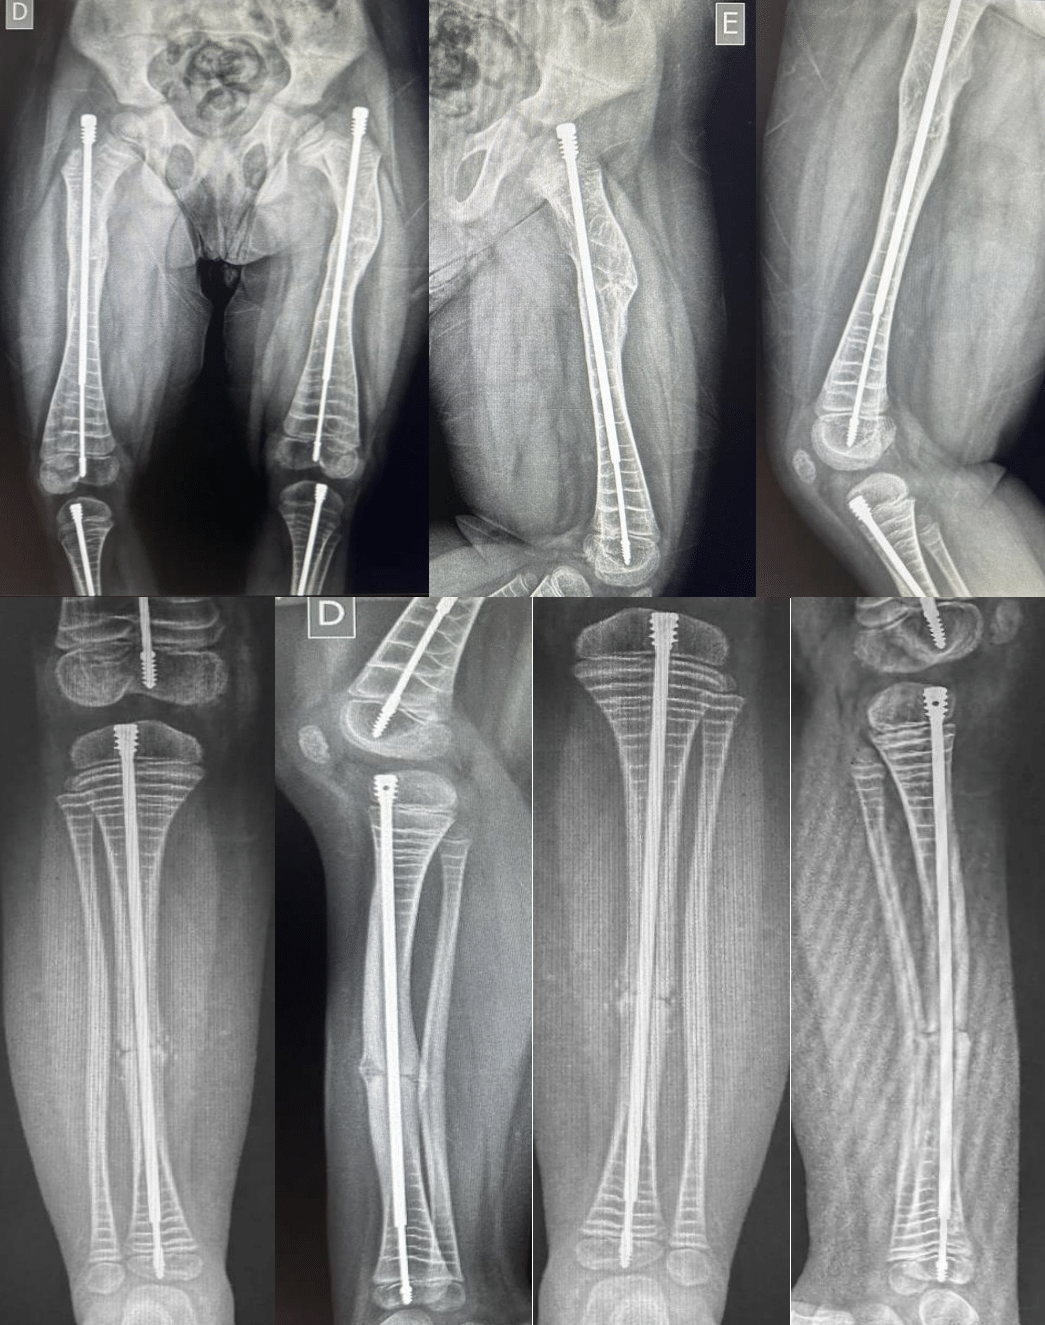

Due to the frequent lower limb fractures and hospital admissions, it was indicated surgical treatment of deformities through osteotomies and fixation with telescopic intramedullary nail. (Figure 1)

Figure 1 Pre-operative X rays where we can see the deformities in anterior and lateral plane of the femur and tíbia.

He was operated for correction of right and left femur on a same surgical time in March 2022. Posteriorly he was underwent right tibia treatment in august 2022 and left tibia in May 2023. (Figures 2)

Figure 2 The corrections of the femurs and tibias, with good alignment.